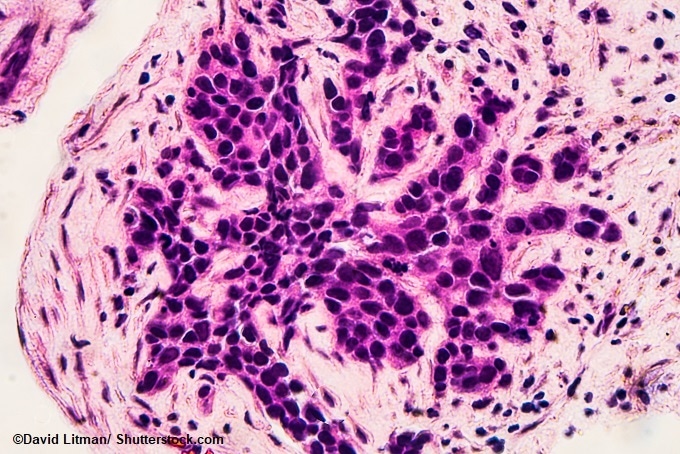

Image: Photomicrograph of core biopsy for infiltrating (invasive) ductal carcinoma, detected by screening mammogram. H & E stain.

In the study, published today in the Journal of the National Cancer Institute, the researchers used immune cell ‘hotspots’ in and around the tumors able to predict a women’s likelihood of breast cancer relapse. They found that women who possessed a large number of hotspots were more prone to relapse when compared with women who had less hotspots.